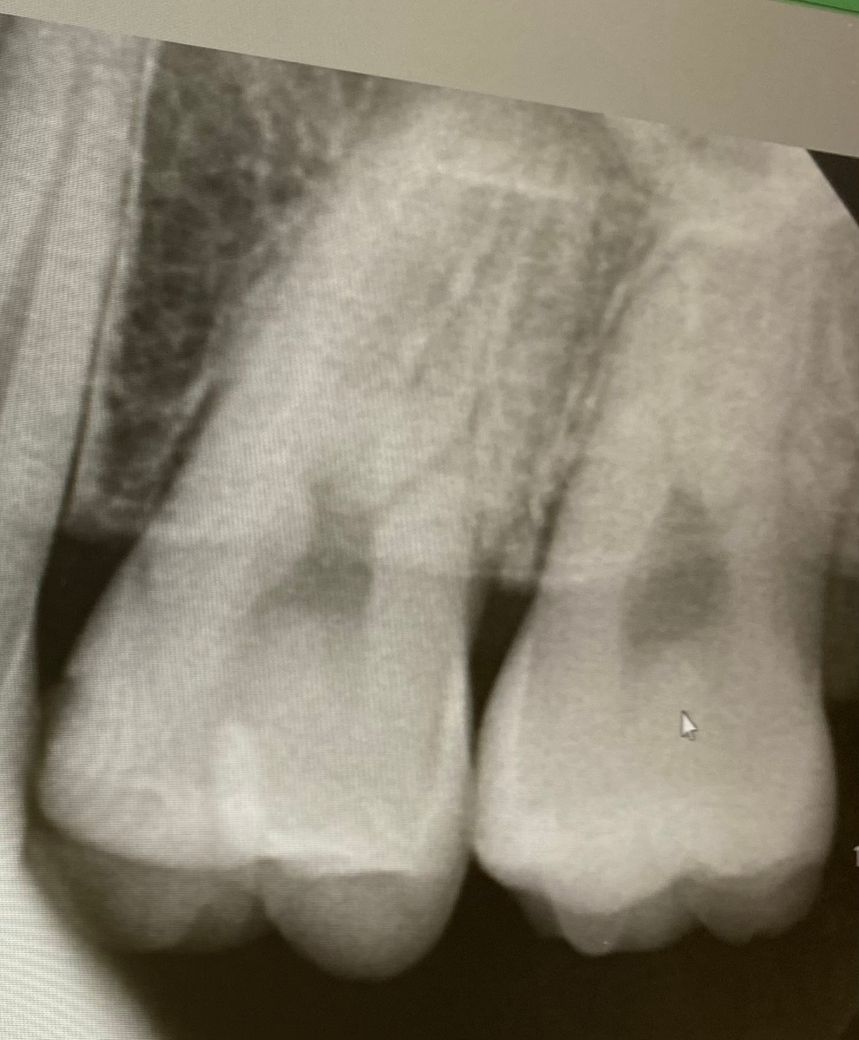

1치과는 충치가 있는 것 같다 양 옆 색상 차이가 있다 눈으로 확인 되는 정도라면 치료 해야 할 시기이다

위치 왼쪽 위 2번째 어금니 치료 한 부위 2차 충치

왼쪽 위 4번째와 3번째 사이 인접면 충치

• 1번 째 사진

사진에 보이는 정도면 충치가 안쪽에 많이 진행됫을 가능성이 있습니다. 저라면 인레이로 치료를 할것같습니다.

육안으로 보였을 경우 인절면에 충치가 있는 것으로 보입니다. 하지만 방사선상에는 크게 보이진 않습니다. 눈으로 보이는 충치가 있기 때문에 인접면 충치는 치료를 하는 것이 좋을 것으로 생각됩니다.

레진보다는 인레이를 하는 것이 일반적이며 레진은 술자를 잘 선택하셔야 합니다. 치료는 필요해보입니다.